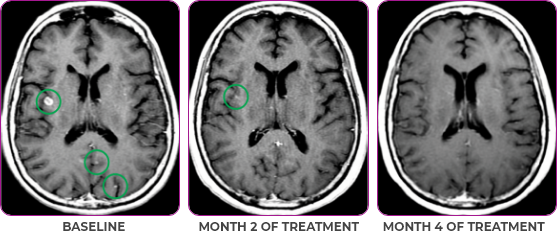

Patient Case - 76 year old - landing

PATIENT CASE:

NSCLCa PATIENT WITH BRAIN

METASTASES1-3

- 76-year-old female with NSCLC that metastasized to the brain and liver

- No prior systemic treatment before trial enrollment

- PRa of primary lung nodules to VITRAKVI® (larotrectinib) confirmed at 2 months1

Response to VITRAKVI1,2

- Partial response to treatment that was confirmed at 2 months (34% tumor reduction)

- Grade 1 cough and Grade 2 fatigue

- Patient remains on VITRAKVI after more than 4 months of treatment

Response in primary and metastatic lesions1

MRIa imagery of the brain. Green circles indicate baseline brain metastases.1

SCAN 2: BRAIN

aMRI, magnetic resonance imaging.